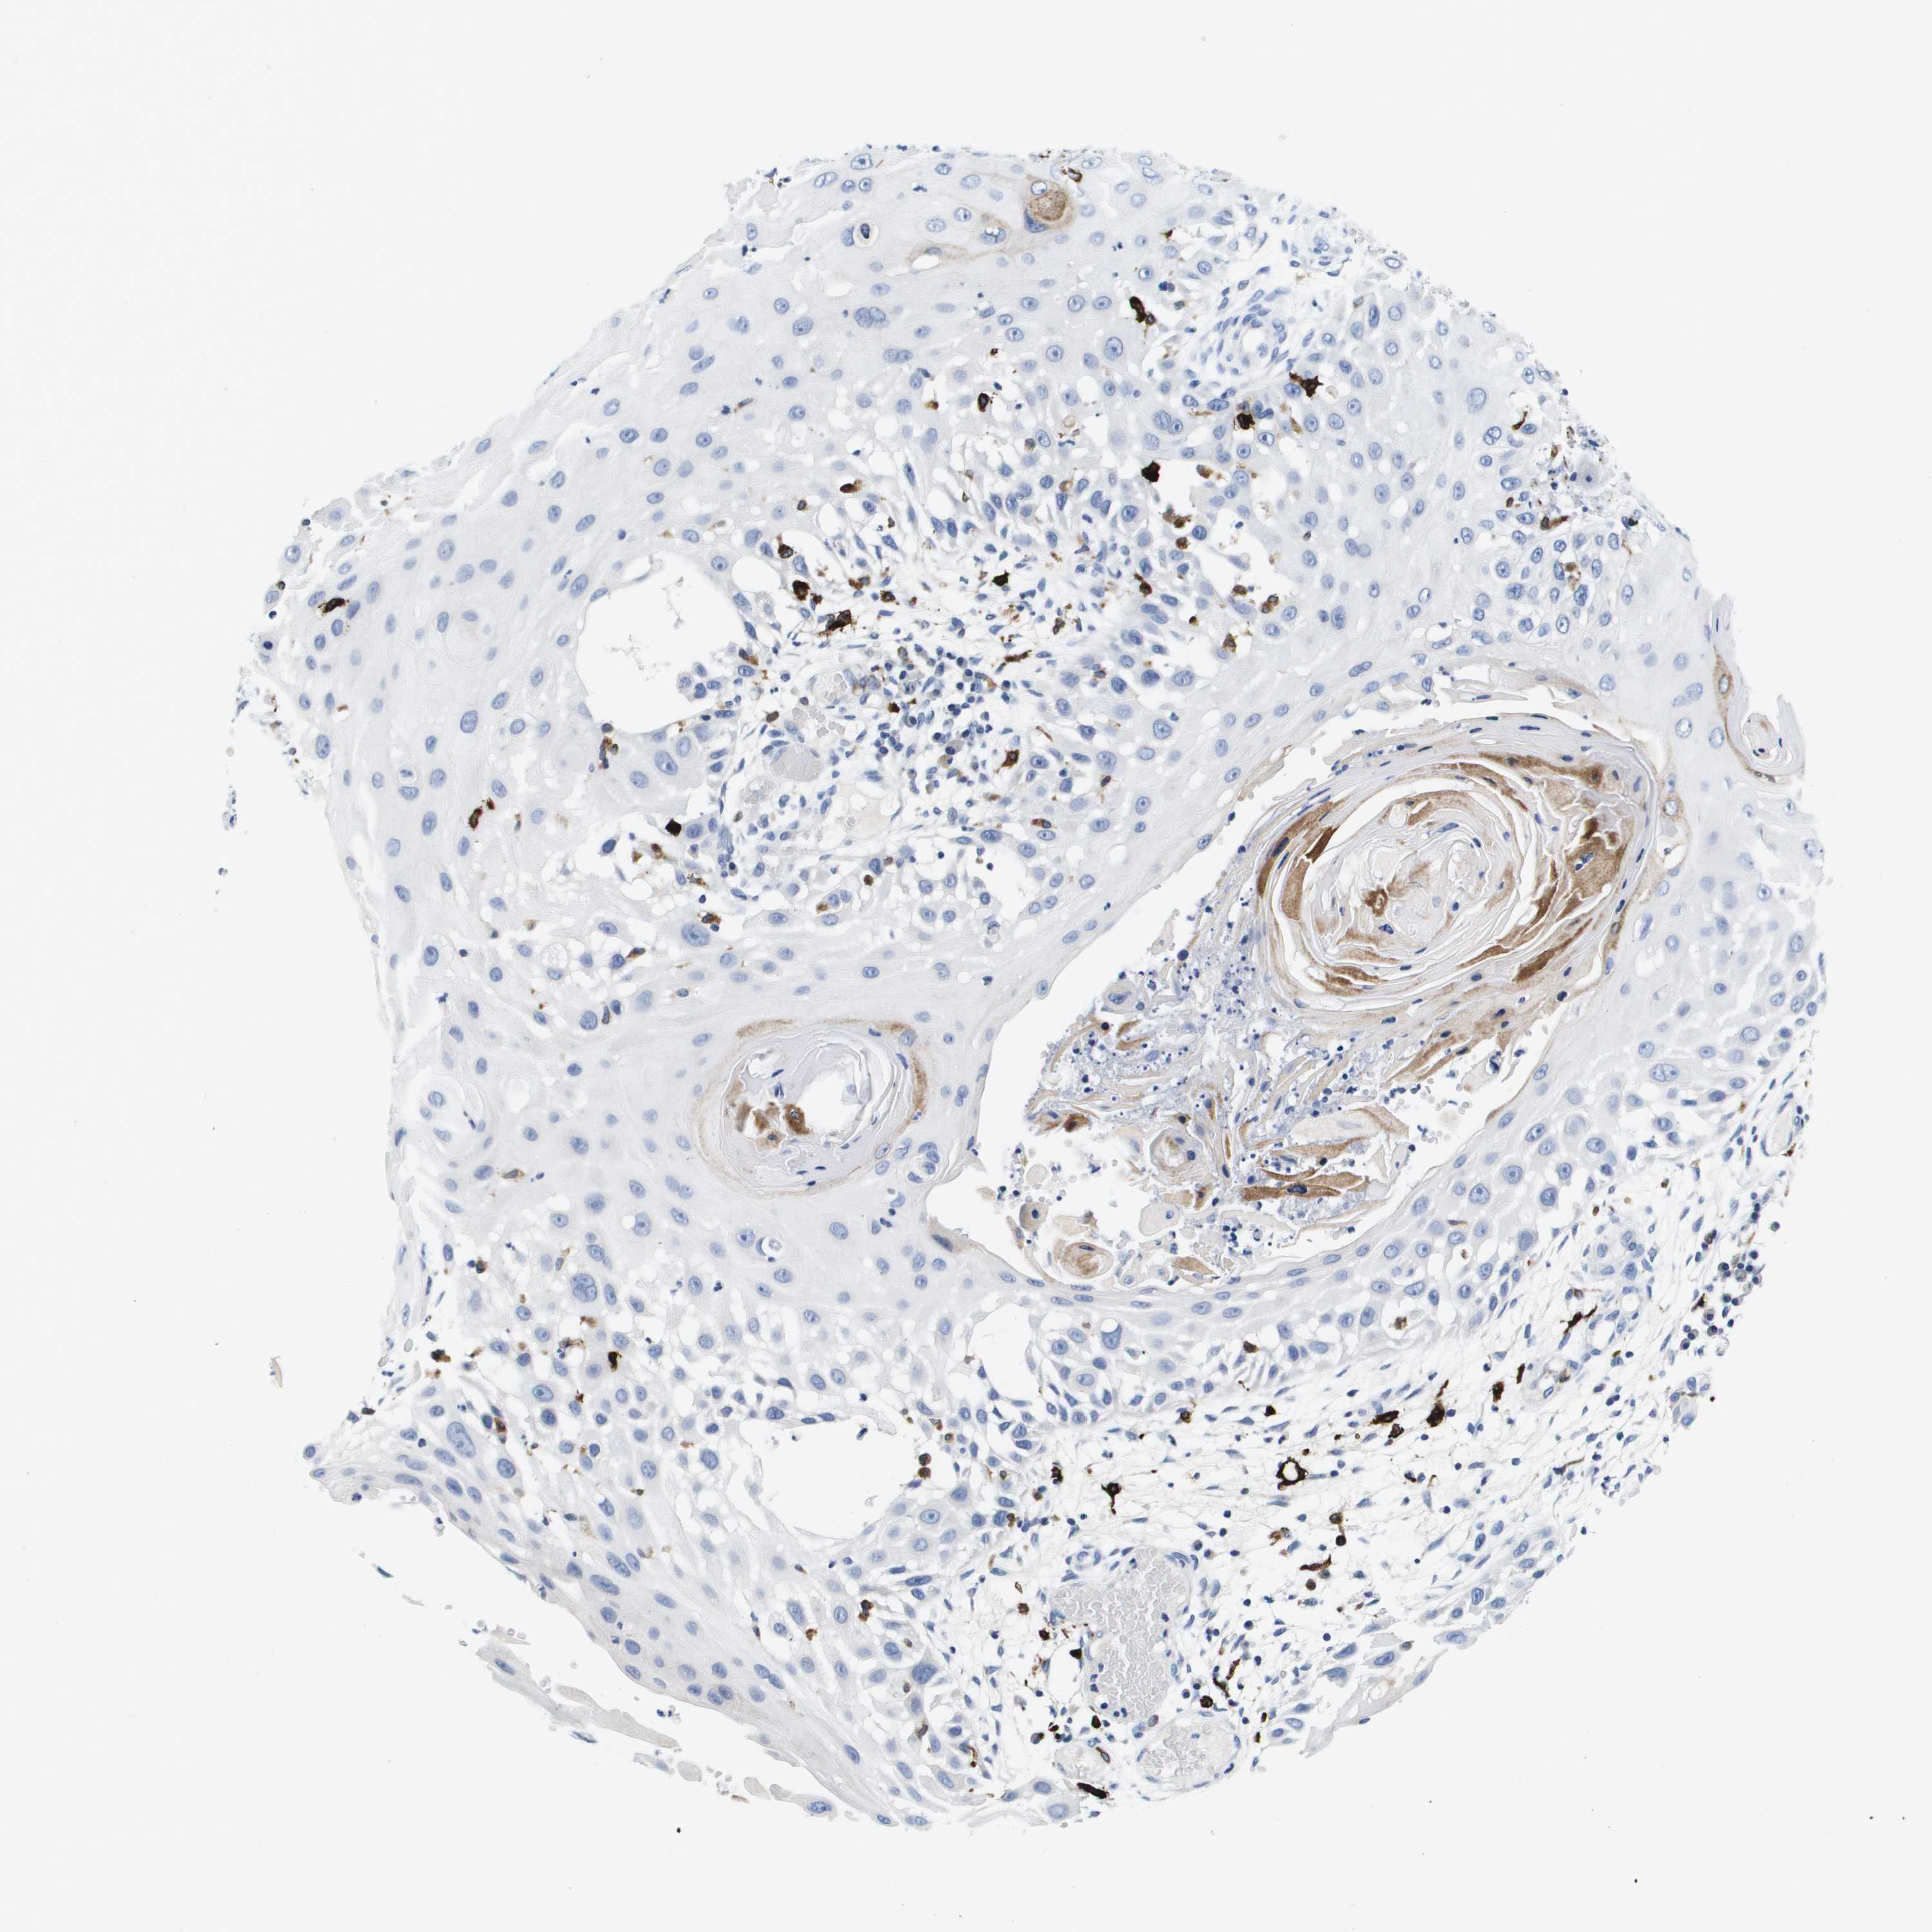

Basal cell and squamous cell cancer

SKIN CANCER - Protein expressioni

A mouse-over function shows sample information and annotation data. Click on an image to view it in a full screen mode. Samples can be filtered based on level of antibody staining by selecting one or several of the following categories: high, medium, low and not detected. The assay and annotation is described here.

Antibody stainingi

Antibody staining in the annotated cell types in the current human tissue is reported as not detected, low, medium, or high, based on conventional immunohistochemistry profiling in selected tissues. This score is based on the combination of the staining intensity and fraction of stained cells.

Each image is clickable and will lead to virtual microscopy that enables deeper exploration of all samples and also displays staining intensity scores, fraction scores and subcellular localization as well as patient and tissue information for each sample.

Antibody HPA000635

Antibody CAB017444

Squamous cell carcinoma, NOS